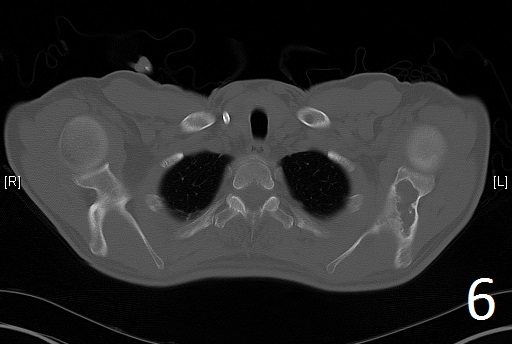

CT

• Useful to determine the extent of the lesion as well as ground glass appearance (Fig. 2-3)

• Well defined borders

• Possible endosteal scalloping lesion

• Areas of mineralization within.

Fig. 6

Fig. 6-7. Axial CT reconstruction of the chest showing lytic and expansile lesion of the left scapula and ribs (polyostotic fibrous dysplasia).